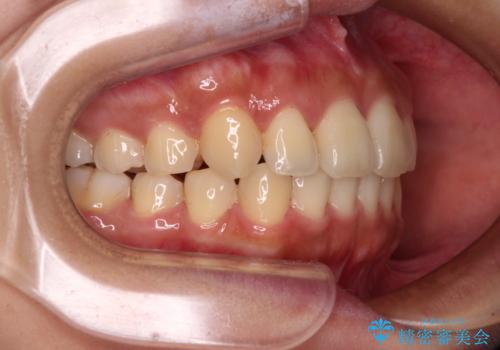

【モニター】歯列が狭くデコボコが気になる 急速拡大装置を用いたインビザライン矯正

- 奥歯の咬み合わせと治療を放置したまま奥歯を気にして来院された患者様です。

上顎骨の幅が下顎骨よりも小さいので、拡大装置により骨幅を広げて上下関係を改善し、その後インビザラインにて歯並びを整えることとしました。

上下の骨幅を改善したことで、スムーズに歯列矯正を行うことができました。

土台のまま放置されていた歯は土台の状態で咬み合っていましたが、急速拡大を行った際に咬み合わせが著しく挙上されたため、その際に土台を大きくすることで咬み合う歯との距離を確保しました。